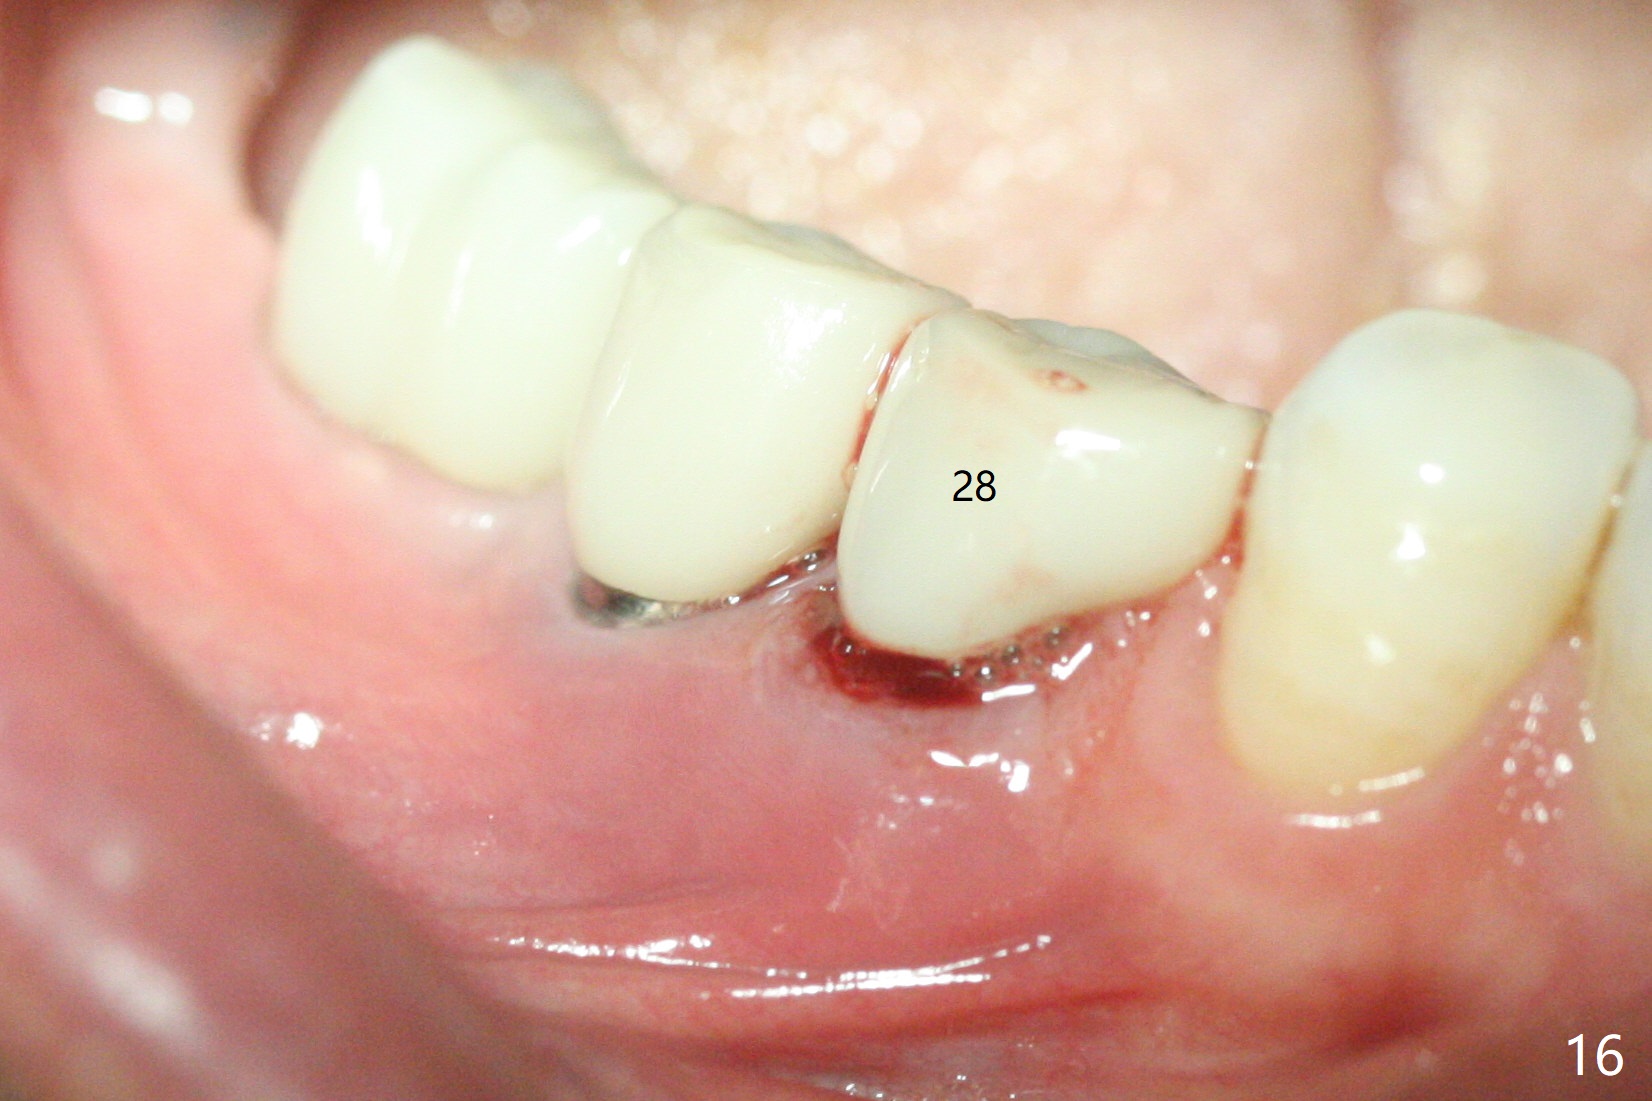

The edentulous ridge at #30 is narrow (Fig.1). After ridge reduction, osteotomy is initiated with 1.2 mm drill for 10 mm; the mesial osteotomy is to be changed (Fig.2 red line). Using a 1.2 mm drill placed in the distal osteotomy (Fig.3 D), the mesial osteotomy changes in trajectory with subsequent placement of a 2.5x10(4) mm 1-piece implant. Since the mesial implant is high in occlusion, the cuff of the distal implant is changed to be 2 mm (Fig.4 (shorter black line)). Panoramic X-ray is taken to show no violation of the Inferior Alveolar Canal (Fig.5 red dashed line). These two 1-piece implants are slightly lingually placed (Fig.6). The crestal bone around the implants resorbs without thread exposure 5 months postop (Fig.7). Impression is taken for a splinted crown (Fig.8-12). There is no metal show around the 2.5 mm 1-piece implants 6 months postop (advantage) vs. that at #28 and 29 (Fig.13). Bitewing is taken post cementation to determine whether residual cement is present (Fig.14). There is periodic swelling and pain in the lower right quadrant 2 years post cementation (Fig.15). In fact periimplantitis appears to have developed at #28 (Fig.16) with loss of the buccal bone (Fig.17,18). The buccal bone loss is less at #29 (Fig.19) and #20 (Fig.23) and no at #30 mesial and distal implants (Fig.20,21). A much smaller implant will be placed lingually at #28 immediate (Fig.24,25).